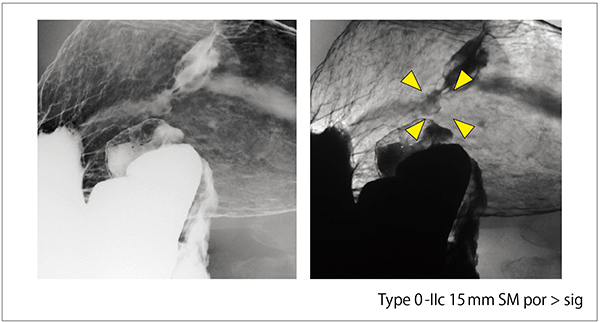

Astorex i9で実際に撮影した胃癌症例を提示する。症例1は、体下部小彎の丈の高い隆起病変であり、小視野や微細視野レベルで粘膜ひだや小区単位の分析が可能であった(図13)。症例2は、噴門部小彎の胃癌例である。明瞭な輪郭を持つたまりの中に、丈の低い隆起部が確認できた(図14)。周囲の粘膜面には大小の不規則な胃小区像が認められるのに対して、病変部では同様の模様像を確認できないことから、本例は粘膜下組織に浸潤した陥凹型胃癌の肉眼的な特徴がX線画像上に現れた症例である、と私どもは捉えている。

図14 Astorex i9による撮影例2